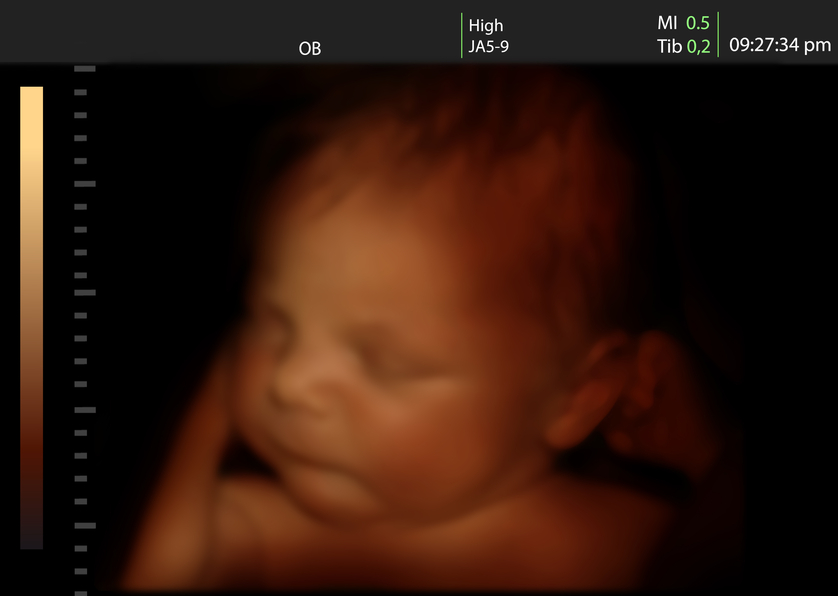

bambino in pancia 3d

Torna a: Settimana 37 di gravidanza